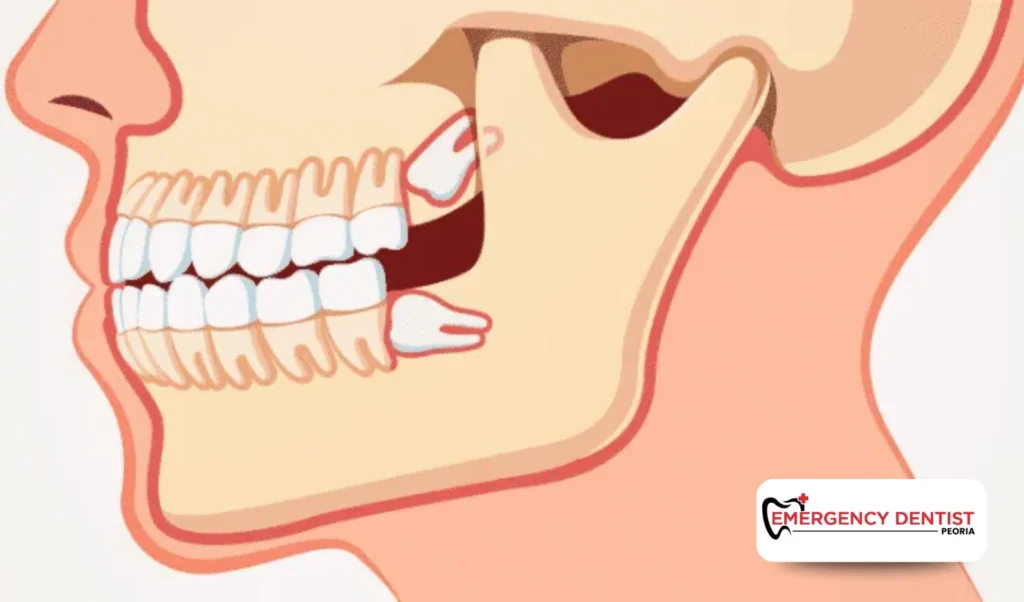

Some wisdom teeth grow straight and are fully erupted, making them easier to remove. Others may be partially visible or trapped under the gum line, increasing the complexity of the dental procedure.

An impacted wisdom tooth does not fully break through the gums. This can lead to pressure, swelling, or infection. Removing impacted teeth often requires oral surgery techniques and careful planning.